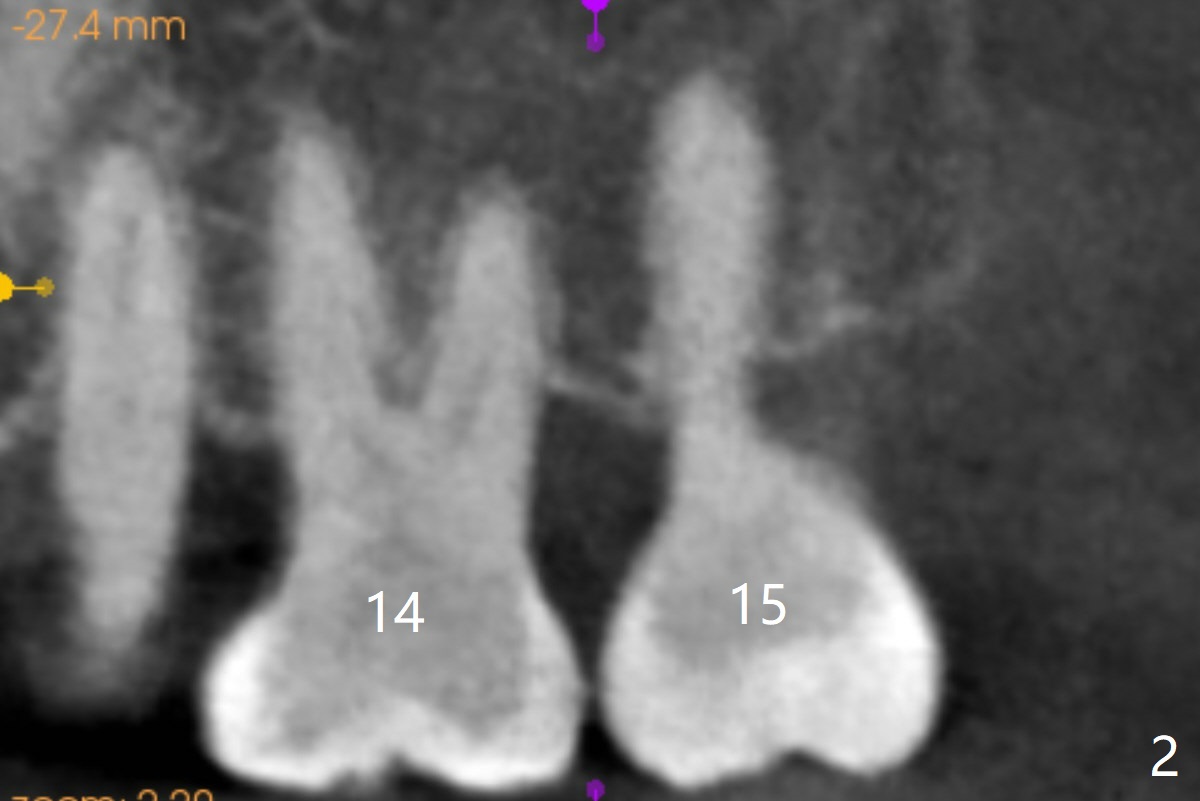

Two months post #19 implant placement, the patient will return to have #14,and 15 supraeruption (Fig.1 arrows) to be taken care of. It appears that there are suitable spaces for mini implants to be placed MP and DB relative to the tooth #14 (Fig.3). Since the palatal (P) mucosa is thicker, a longer mini-implant is expected (8 or 10 mm) palatally, vs. 6 or 8 mm buccally.